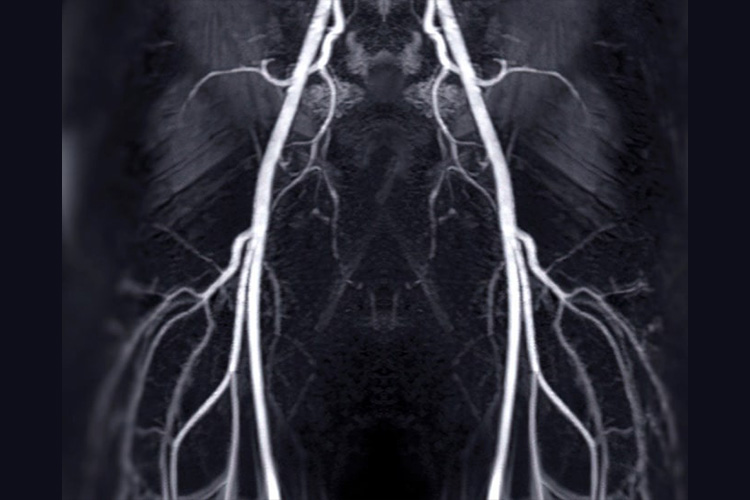

④MRI検査

MRIのイメージ

MRI(磁気共鳴画像撮影)とは、電磁気の力を利用して体の内部を撮影する装置です。CTのように放射線被ばくを心配することもありません。